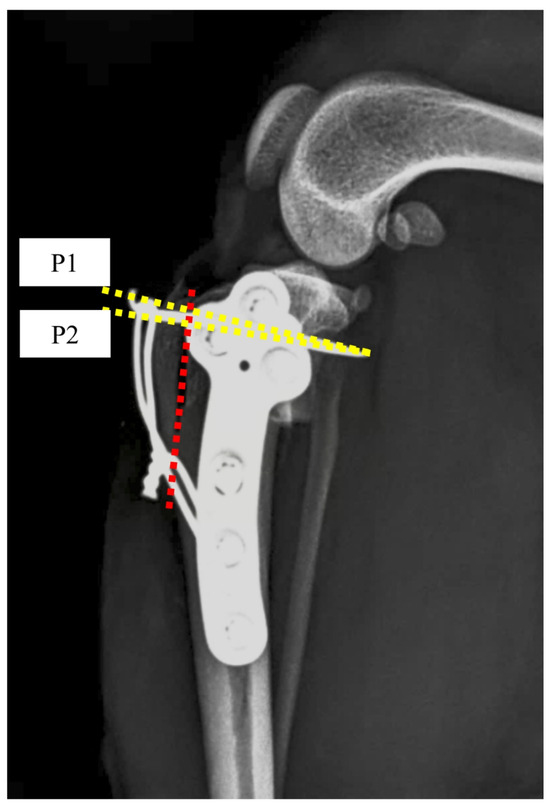

2.3. Radiographic Measurements

- Dismukes, D.I.; Tomlinson, J.L.; Fox, D.B.; Cook, J.L.; Song, K.J.E. Radiographic measurement of the proximal and distal mechanical joint angles in the canine tibia. Vet. Surg. 2007, 36, 699–704. [Google Scholar] [CrossRef]